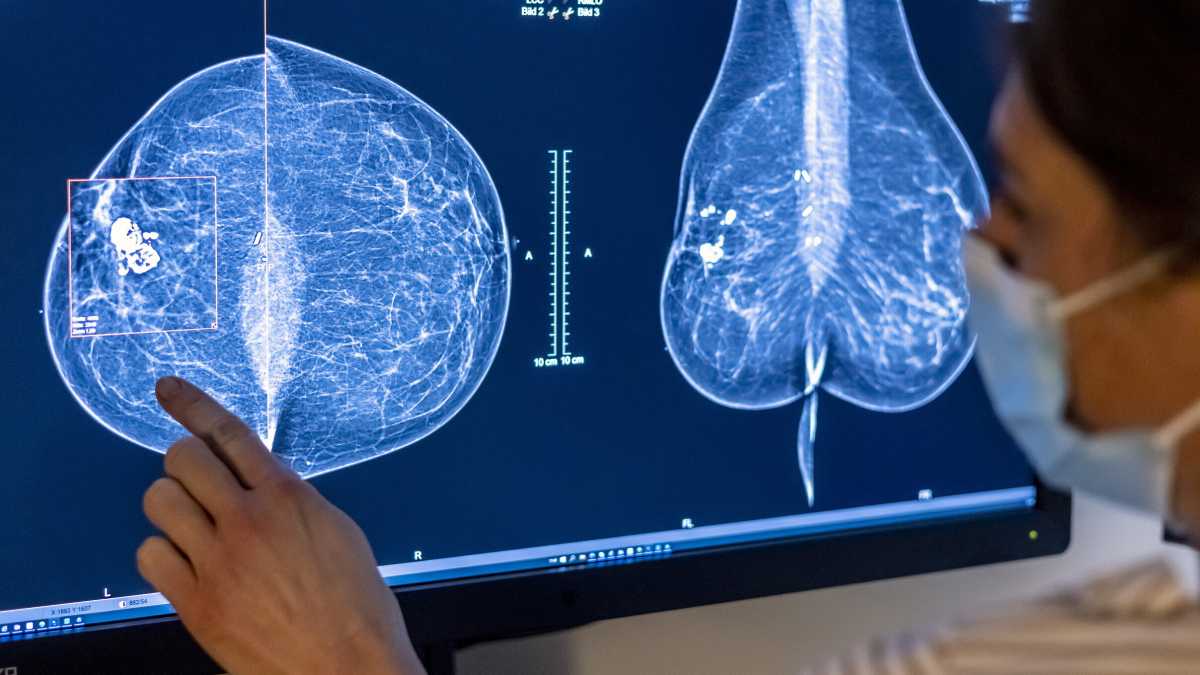

Berlino, il personale medico usa una mammografia per esaminare il seno di una donna (Foto di Michael Hanschke/Getty Images)&nbsp;<br />

In questo contesto si inserisce un recente studio appena pubblicato su Nature Medicine, che analizza come l'IA possa essere utilizzata per migliorare lo screening mammografico e il rilevamento del cancro al seno. Questo studio è stato condotto in Germania e ha coinvolto oltre 460.000 donne, con l'obiettivo di valutare l'efficacia di un sistema IA nel supportare i radiologi durante la doppia lettura delle mammografie, un processo essenziale per garantire la qualità degli screening. I risultati mostrano che l'IA ha permesso di scoprire più tumori senza aumentare inutilmente i falsi allarmi, riducendo anche il carico di lavoro per i radiologi.